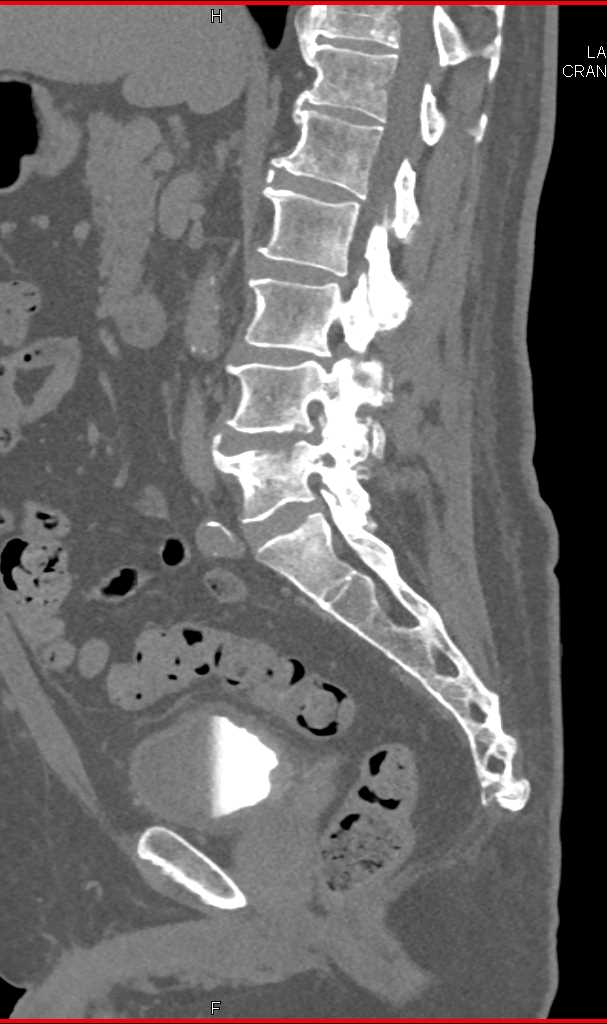

Infection at L4-L5 interspace